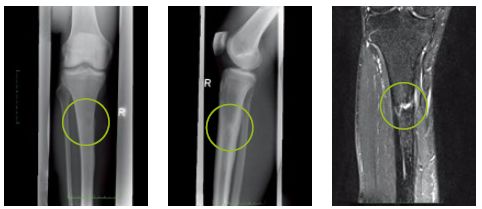

应力性骨折

症状:

●早期的应力性骨折通常表现为骨挫伤,也可能会伴随其他损伤(如前交叉韧带撕裂)。

●下肢没有受到过外部激烈的碰撞而出现突然性疼痛,而且这种疼痛使人不能继续跑步,或者很难继续跑步。

●单足站立时局部出现疼痛,或者单足跳时出现疼痛。

●用手指压痛处时出现钻心的疼痛感。

●疼痛点在完全停止跑步后在一段时间内会自然消除。